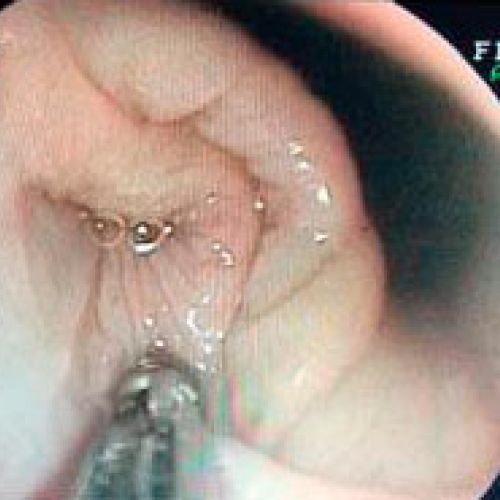

Endoscopia rígida y endoscopia flexible

En CiruVET realizamos procedimientos diagnósticos, como las endoscopias de última generación

En CiruVET contamos con el equipo necesario para los diferentes procedimientos diagnósticos y terapéuticos a nivel respiratorio y digestivo. En resumen, realizamos las siguientes pruebas diagnósticas: